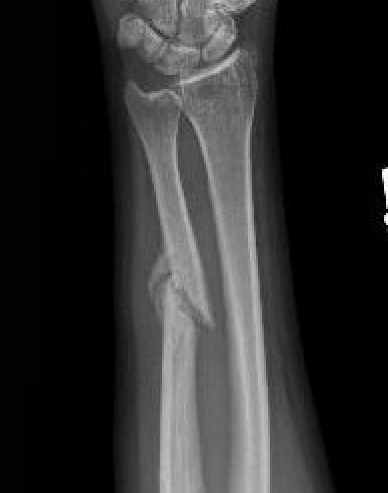

Night stick injury - direct blow or trauma to ulna

Distal 1/3

Midshaft / middle 1/3

Proximal - beware Monteggia / radial head dislocation

Nonoperative management

Indications

Minimally displaced fractures

- < 50% displaced

- < 10 degrees angulation